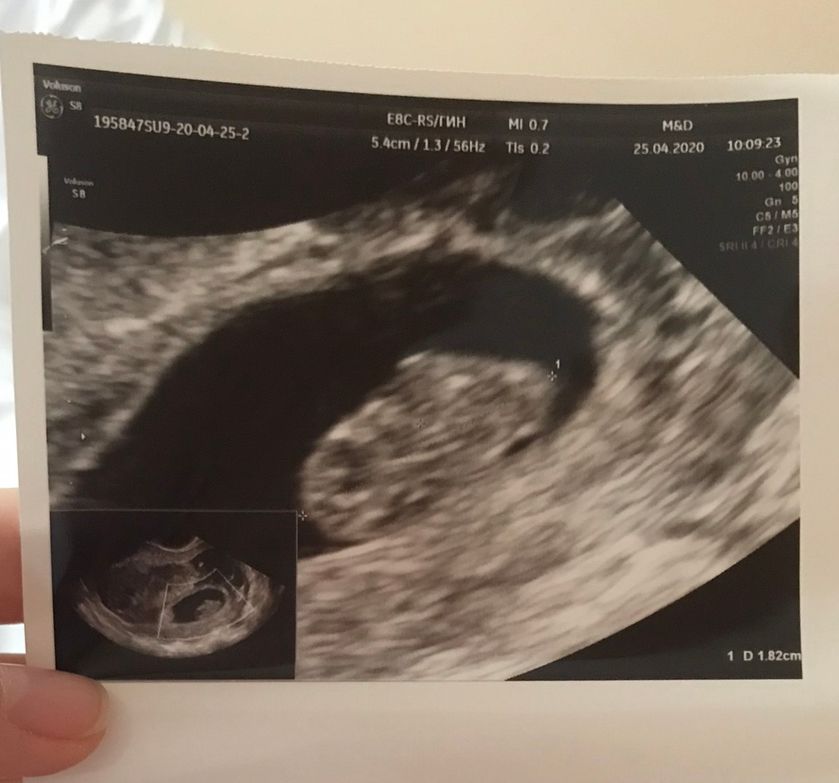

Катя, у вас просто другой масштаб и ракурс, вот узи через 3 дня после предыдущего фото: Изображение А вот ещё через 2 дня: Изображение